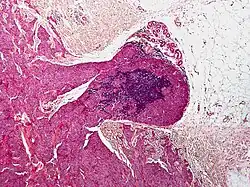

Micrograph of a blue nevus showing the characteristic pigmented melanocytes between bundles of collagen. H&E stain.

Micrograph of a blue nevus showing the characteristic pigmented melanocytes between bundles of collagen. H&E stain. Blue nevus